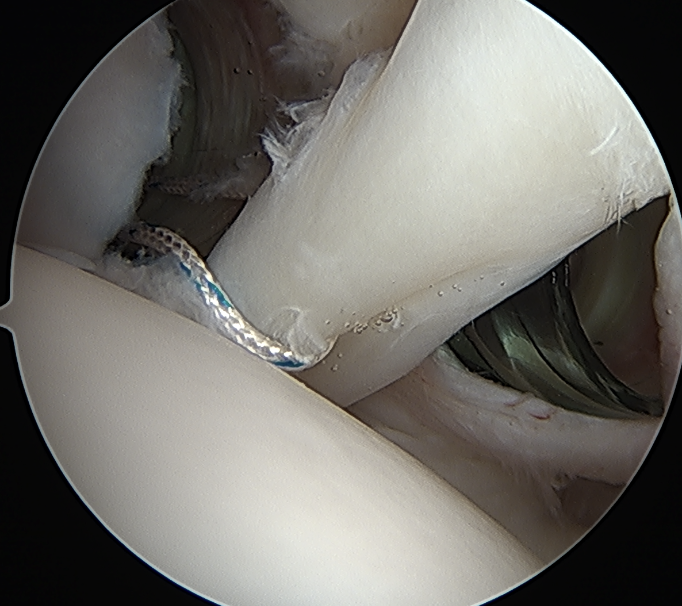

Tag biceps and release

Anchor biceps tendon into bicipital groove